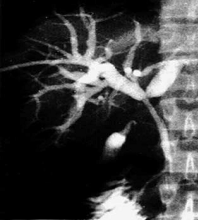

Совершенствуются эндобилиарные рентгенохирургические вмешательства. При обтурационной желтухе посредством чрескожной пункции и катетеризации желчных протоков выполняют их декомпрессию и создают отток желчи - наружное или внутреннее дренирование желчных путей. В желчные пути вводят препараты для растворения небольших конкрементов, с помощью специальных инструментов удаляют из протоков мелкие камни, расширяют билиодигестивные соустья, в частности анастомозы между общим желчным протоком двенадцатиперстной кишкой при его сужении. У резко ослабленных больных с острым холициститом осуществляют чрескатетерную облитерацию пузырного протока, после чего проводят противовоспалительную терапию, заверщающуюся дроблением и удалением конкрементов. Все большее применение находит чрескожное наложение гастростомы, еюностомы, холицистостомы. Для устранения сужений пищеварительного канала, в т.ч. пищевода, проводят баллонную дилатацию.

Эндопротезирование желчных путей